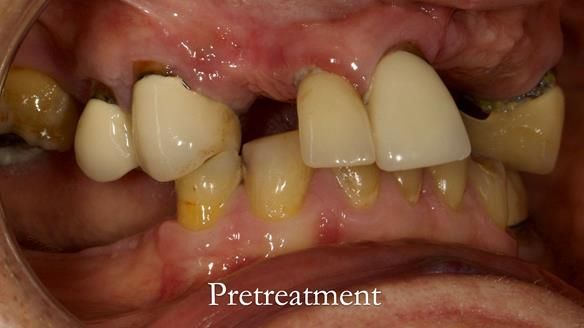

Aesthetically and functionally poor RPDs were replaced for Eileen, a 74 year old woman.

Referred to me by her general dental practitioner specifically for replacement RPDs.

Diagnoses

- Missing teeth in the upper and lower jaws

- Upper and lower metal based RPDs, poorly fitting, worn occlusal surface, reverse curve aesthetics, lacking support

- Poor dental appearance with reverse incisal curve

- The upper right central and lateral incisors with post crowns. Healthy and functionally secure but with poor appearance, contributing to the reverse curve.

- Moderate to heavily restored dentition with deep overbite (Class 2 div II)

- Yellowish lower front teeth with small amount of wear.

- The lower right canine (LR3) is worn with MOD cavity.